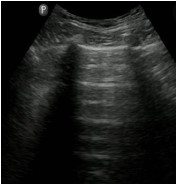

Paciente de 70 anos do sexo masculino dá entrada no Pronto-Socorro após iniciar quadro de dispneia em churrasco, há cerca de 1 hora.

Relata ser hipertenso e ter insuficiência cardíaca. Ao exame clínico, dispneico, FR 30, SatO2 77% em ar ambiente, FC 110 e PA 190x120, com ausculta pulmonar com estertores finos até ápices.

Assinale a opção que apresenta a imagem de ultrassonografia pulmonar compatível com a descrição do quadro acima.